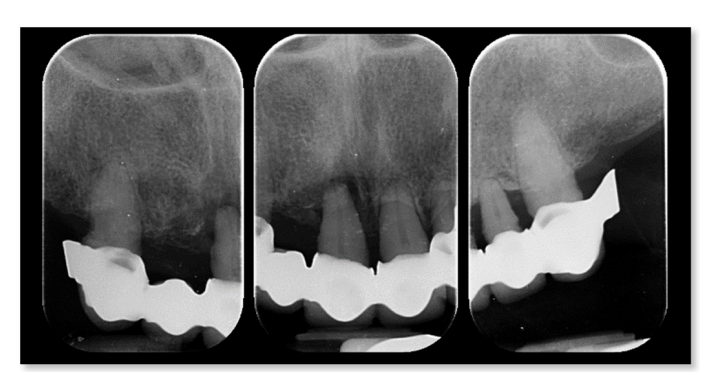

Ниже представлен объяснительный клинический случай. 62-летняя женщина обратилась за вторым мнением из-за существующих съемных частичных протезов, закрепленных на оставшихся естественных элементах, которые были установлены несколько месяцев назад. При клиническом и рентгенологическом обследовании пациентка предъявила основные жалобы на подвижность зубов, кровоточивость десен, боль, дискомфорт, плохую функцию и неэстетичный внешний вид (Рисунки 1 и 2).

Окончательным решением стало переделка обеих реабилитаций. По экономическим причинам пациент вернулся к предыдущему стоматологу с просьбой решить все проблемы. Однако, спустя шесть лет, пациент снова обратился с просьбой решить её жалобы, так как они не были рассмотрены. Предварительные клинические и радиологические анализы показали безнадежное остаточное зубное состояние, характеризующееся тяжелым хроническим периодонтитом, подвижностью, кровоточивостью десен и болью в остаточных верхних зубах, а также одиночным клыком в нижней челюсти. Эстетика и функция также были серьезно нарушены, так как пациент не носил съемные частичные протезы в течение многих лет.